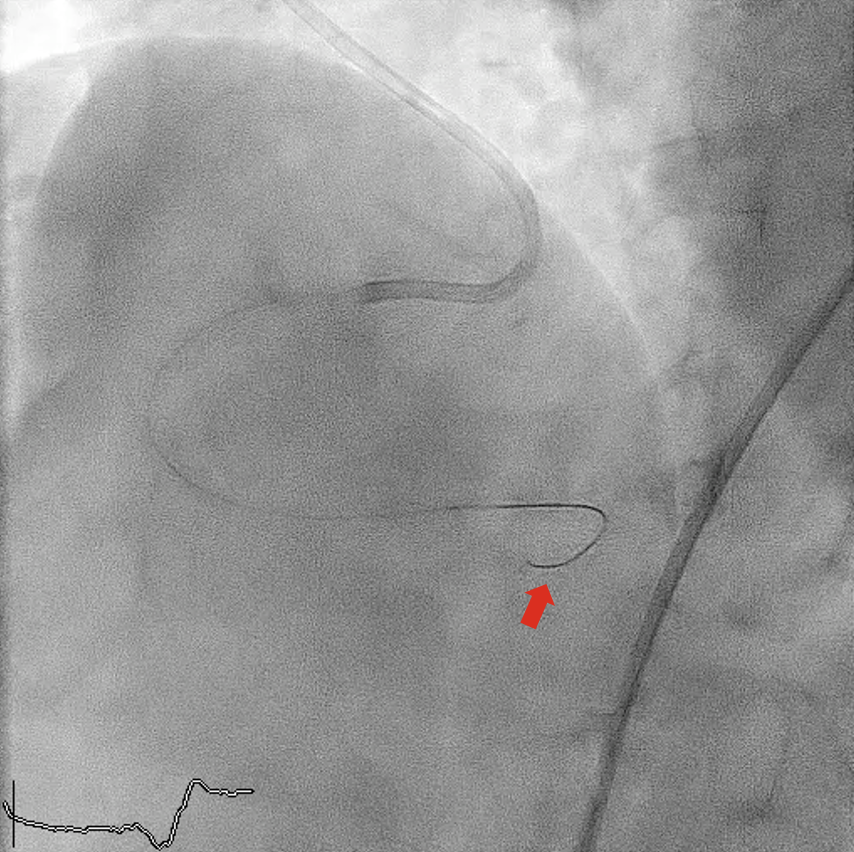

After arrival in the coronary care unit, the patient’s BP returned to his baseline high BP of approximately 190/90 mm Hg; oral antihypertensive was given. One hour later, the patient suddenly developed ventricular fibrillation, which was successfully defibrillated. Echocardiogram showed no pericardial effusion.

Urgent angiography revealed perforation of a small posterior descending artery branch (Figure 4, Videos 3A and 3B), likely from guidewire trauma (Figure 5). Prolonged balloon tamponade failed; successful sealing was achieved with a 2.0 × 20-mm Nester embolization coil (Cook Medical) (Figure 6, Video 4). No further events occurred.

The final coronary angiography of the first PCI was reviewed in details and no distal perforation was revealed. It was likely that the perforation was concealed at the end of the first PCI because of the much lower BP. The delay in presentation was then likely related to the subsequent significant rise in BP, resulting in clinically manifested perforation.